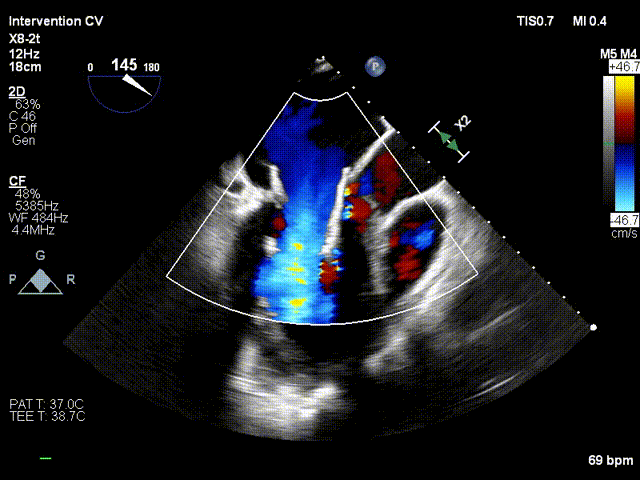

TMVR术后

术后第2天患者出监护室,术后第4天拔管,术后第5天顺利出院。出院前心超显示:经导管二尖瓣人工瓣膜植入术后,人工瓣膜支架固定,形态未见异常,瓣叶开放不受限,瓣口由多普勒估测其开放峰值流速为1.15m/s,峰值压差5mmHg,平均跨瓣压差为2mmHg,由连续多普勒据PHT估测面积约2.93cm²,瓣叶关闭形态未见异常,彩色多普勒未测及二尖瓣反流及瓣周漏;左心室流出道通畅,流出道峰值流速0.93m/s。

出院时人工瓣膜开口面积

出院时人工瓣膜跨瓣压差

出院时Neo-LVOT